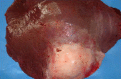

The study was carried out at Nyala abattoirs, South Darfur State, Sudan during a period from 2009 to 2011. Slaughtered camels (822) were examined for pathological changes of liver abscesses and identification of the involved aerobic bacteria. Grossly, a total of 111 (13.5%) liver abscesses were recorded in different camel ages; 90 (81.1%) were less than seven years old and 21 (18.9%) were more than seven years old. Histopathology of sectioned tissues revealed necrotic abscesses with infiltration of inflammatory cells, hydropic degeneration with swelling of hepatocytes comprising the sinusoid and different size of vacuoles in the hepatic cells. Proliferation of bile ducts with fibrous tissue and infiltration of inflammatory cells was also recorded. Investigation of bacteria revealed 90 aerobic isolates; they were identified to 52 (57.8%) gram positive cocci, 20 (22.2%) gram positive rods and 18 (20.0%) gram negative rods. Staphylococcus spp. (41.1%), Corynebacterium spp. (17.9%) and Streptococcus spp. (13.3%) were the most frequently identified bacteria involved in liver abscesses of camels in the region. Further studies are required to assess the pathogenicity of bacterial isolates from camel livers. This is particularly important from a public health perspective, since some people of Sudan are known to consume raw camel liver.